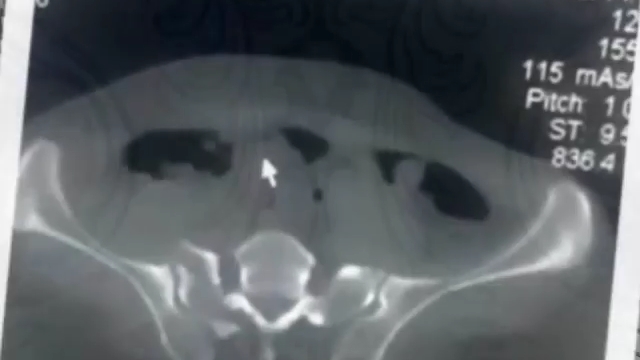

شکستگی حلقه لگنی

شکستکی حلقه لگنی جزو مشکل ترین و پر عارضه ترین آسیب‌های بدن هستند.